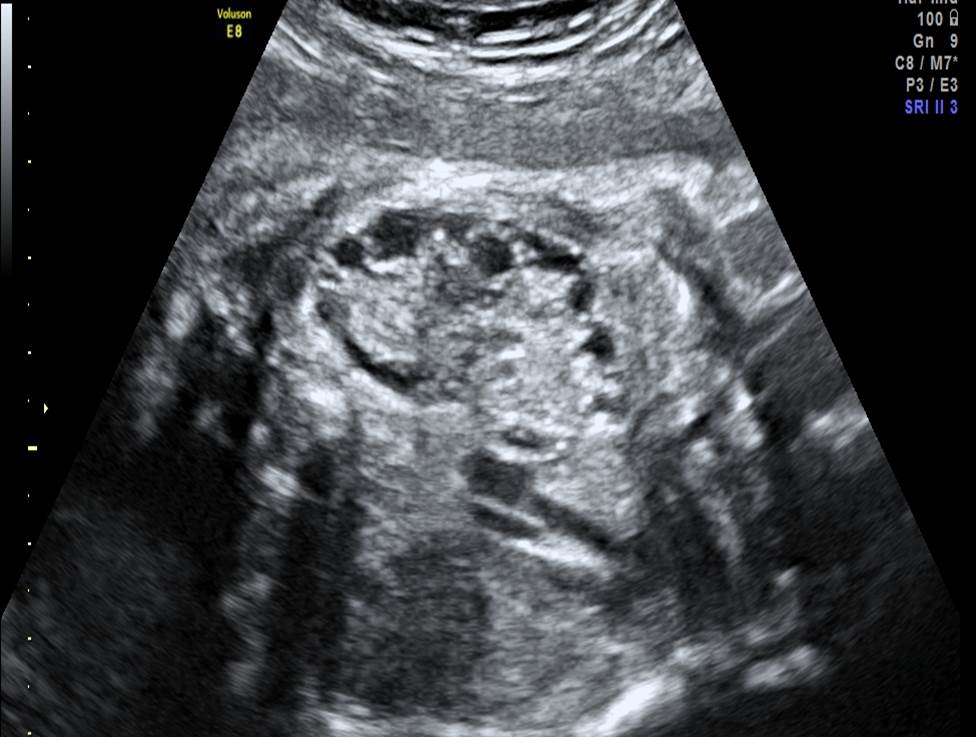

Проанализируйте изображения первого плода из дихориальной двойни в 24 недели (плод мужского пола), установите диагноз и дальнейшую тактику ведения беременности